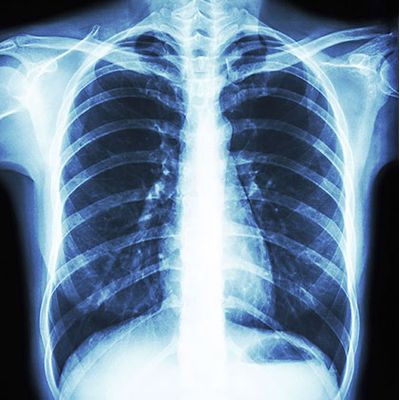

Cardiothoracic Radiology encompasses all modes of imaging of the thorax including the chest, lungs and heart. Practitioners are responsible for all conventional chest radiography, CT and MRI. Greensboro Radiology is proud to offer sub-specialty trained Cardiothoracic expertise including high-resolution CT for interstitial lung disease as well as screening programs for coronary artery disease and lung cancer. The service is fully digital and integrated with our colleagues in thoracic surgery and pulmonary medicine.